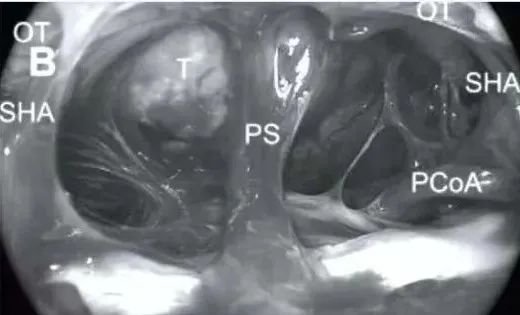

(B)鞍膈上区暴露及结构识别:暴露鞍膈上区,并识别以下重要结构,垂体柄 (PS)、后交通动脉 (PCoA)、垂体上动脉 (SHA)、视神经 (OT)、肿瘤 (T)。

(C)肿瘤切除,膜外钝性剥离:使用钝性器械在肿瘤外包膜外进行剥离,逐步切除肿瘤。注意观察垂体柄 (PS) 的位置,本例中垂体柄受肿瘤压迫向左侧偏移。